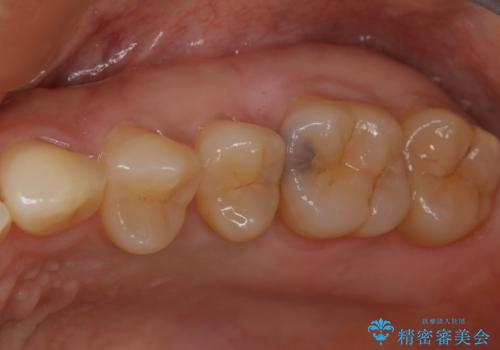

大臼歯 大きな虫歯をセラミックインレーに

- 歯が黒くなってきているのが気になるとのことで、レントゲンを撮影し診断を行いました。

幸い神経までは到達していない虫歯だったため、部分的な詰め物「インレー」で治療を行うこととなりました。